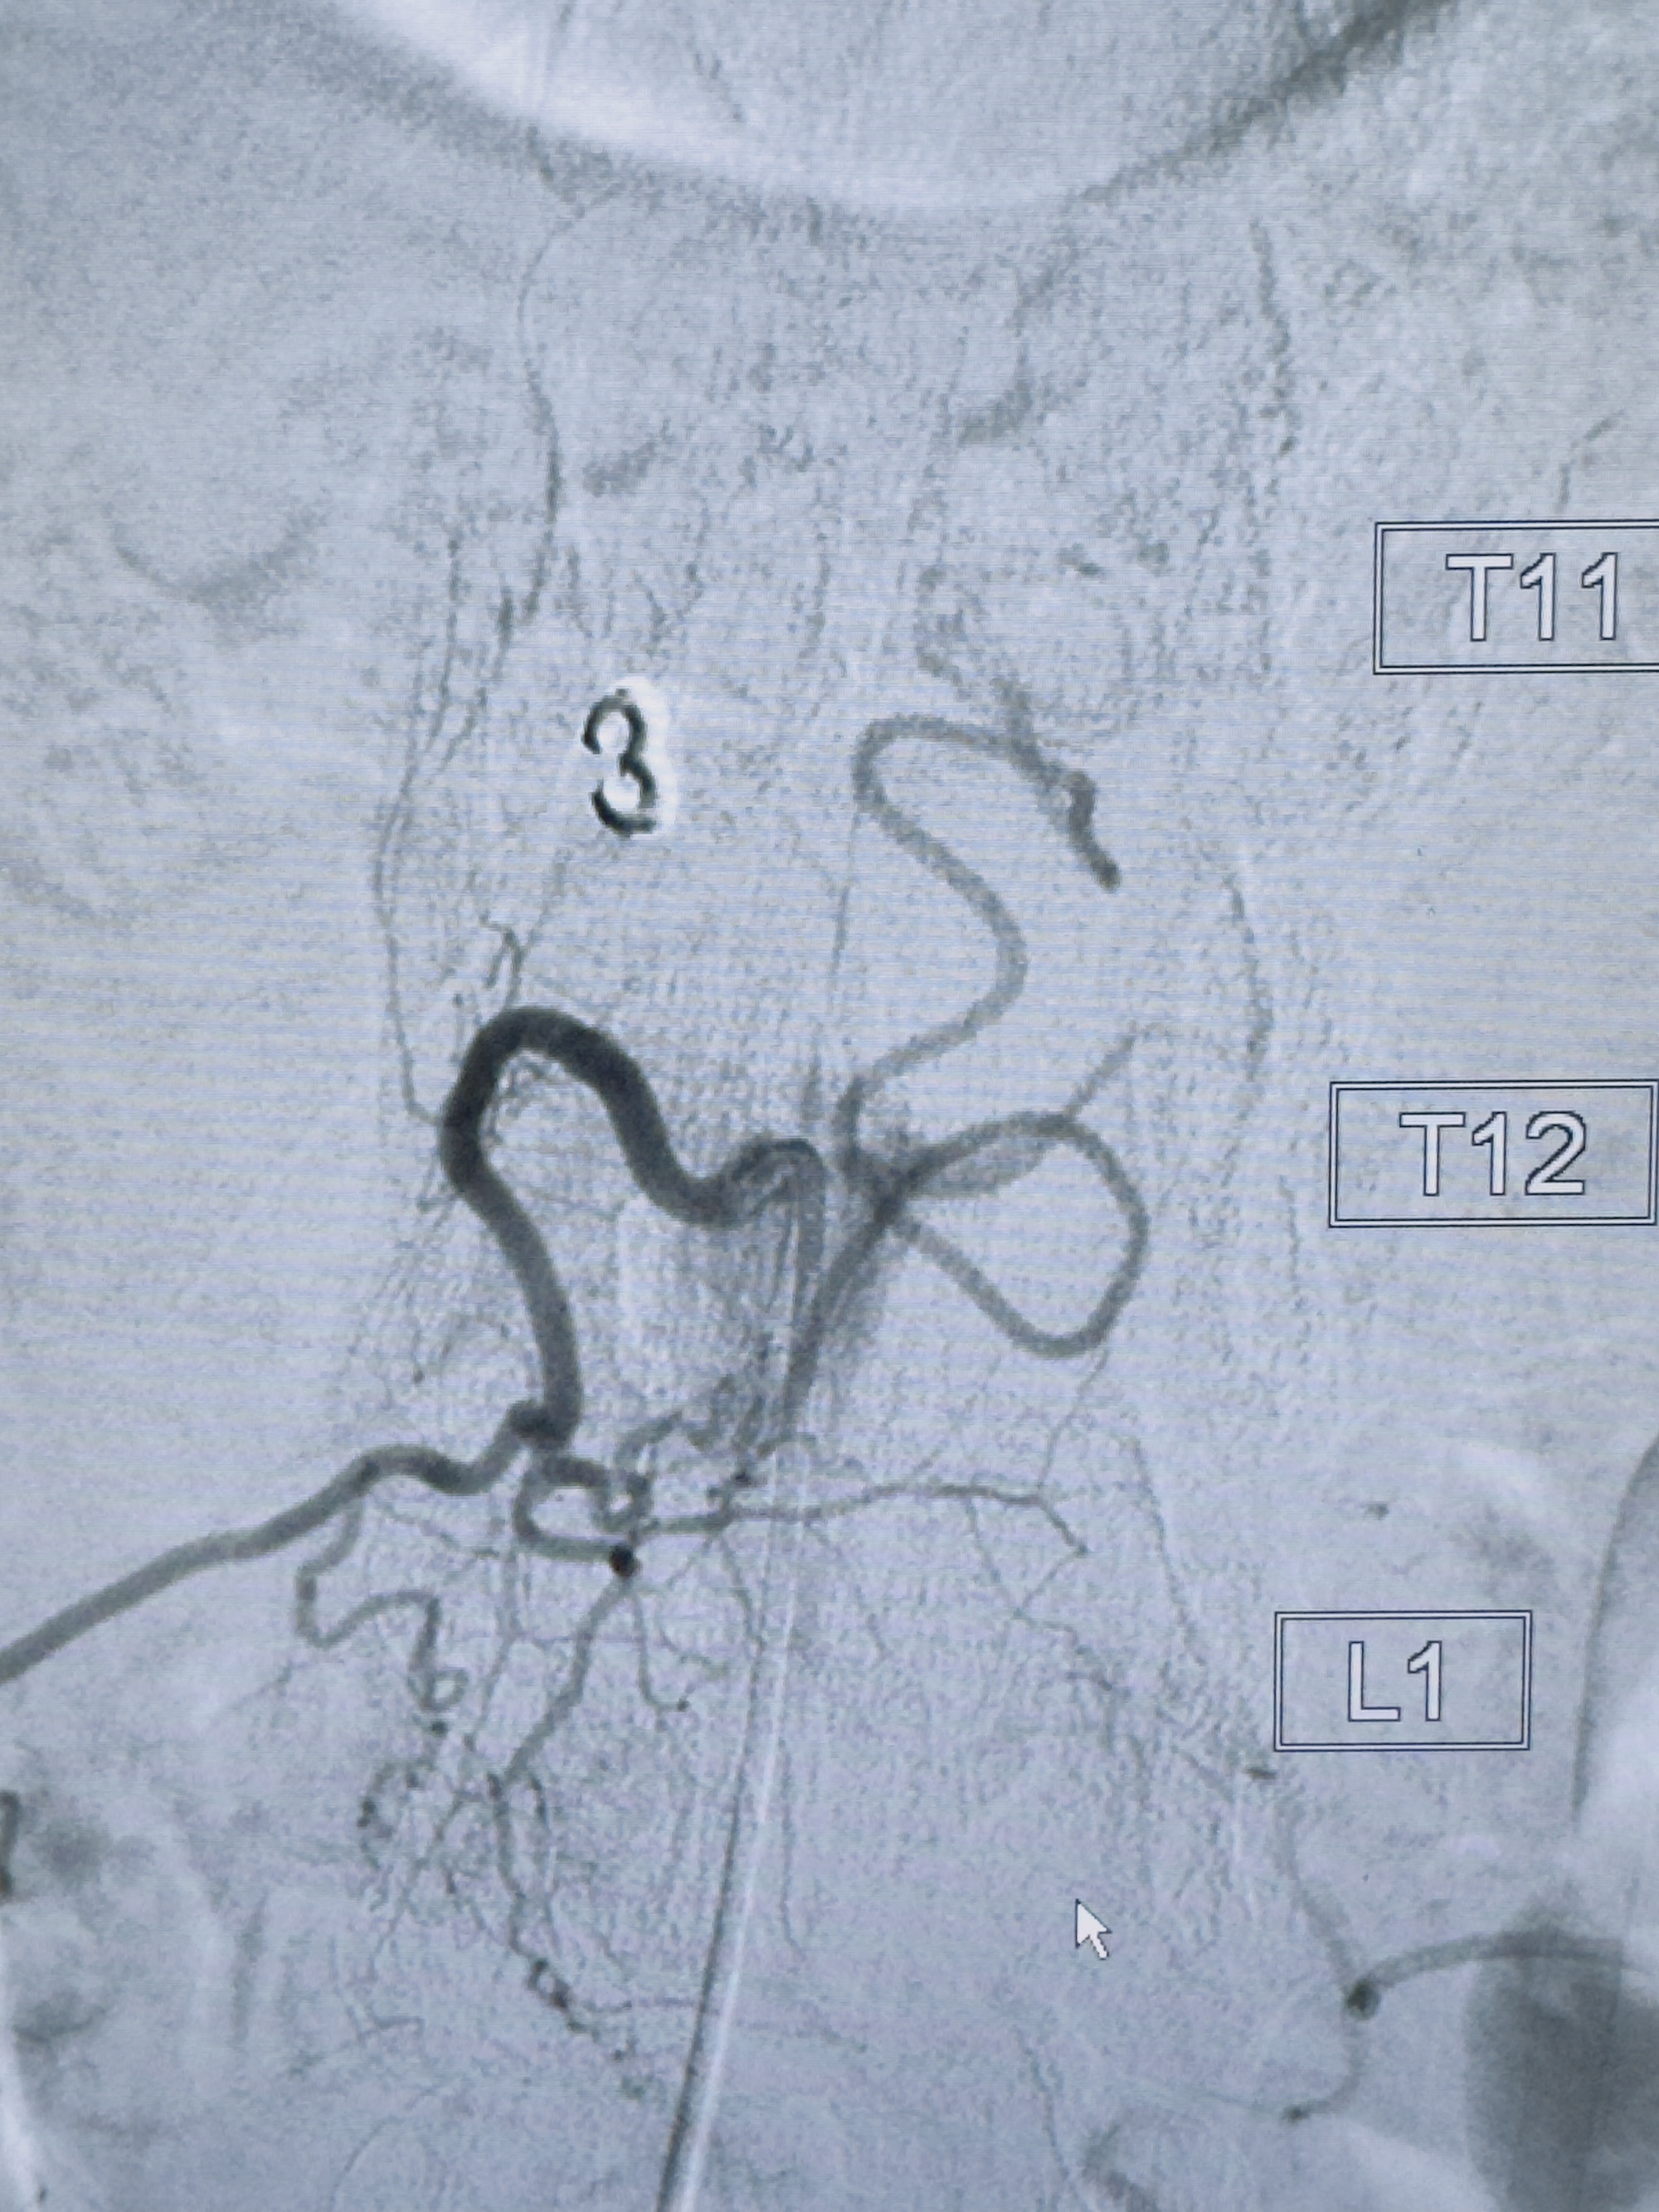

2023-10-13DSA:右侧L1水平硬脊膜动静脉瘘,供血动脉为右侧L1,附近动脉未见明确吻合供血,供血动脉处可见脊髓前动脉发出